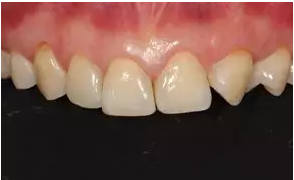

術(shù)后上前牙正面照

病例分享|復(fù)合樹脂微創(chuàng)美學(xué)修復(fù)關(guān)閉上前牙間隙